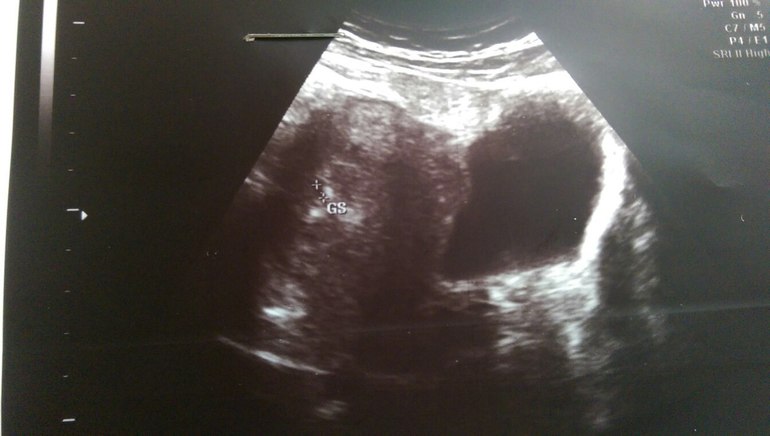

- Беременность есть! Маточная!Плодное яйцо вот вот недавно только опустилось!!!!Всё хорошо, всё на месте ,угроз и всего прочего не видно!

Беременность маточная ,раннего срока (3недели 6 дней)

Средневнутренний диаметр 0,39 см,желточный мешок не визуализируется.